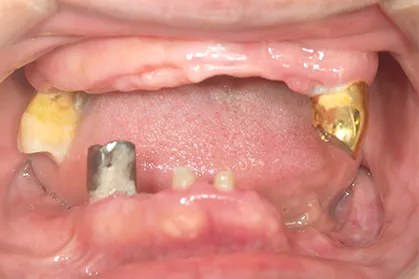

- BEFORE

| 年代・性別 | 70代・男性 |

|---|---|

| 主訴 | 今使っている入れ歯が合わず、嚙むと痛い |

| 治療部位 | 15~26、36、45 |

| 治療内容 | 上下顎インプラント埋入術(上顎5本、下顎2本)を、2回に分けて実施。26部はソケットリフトを適用し、2回法で実施。他部位は1回法。 |

| 金額(税込) | 29,000,000円(税込) |

| 治療期間 | 7カ月(インプラント埋入から上部構造装着まで) 12年経過例(2024年3月時点) |

| リスクと副作用 | 手術部位の腫脹、疼痛 マスダ歯科のインプラント詳細はこちら |